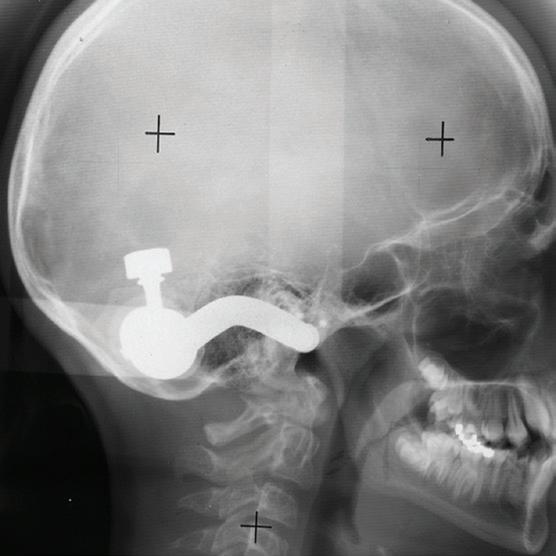

Project Title: The impact of TMJ mechanobehavior on outcomes of mandibular advancement surgery

This project will use clinical tools previously developed by our research team to identify factors that may contribute to the loss of mandibular condylar structure (resorption) following orthognathic surgery to advance the mandible. Specifically, we will combine individual-specific information about jaw mechanics and behaviors plus psychosocial and physiological conditions to compare these before and after surgery. In particular, how much and how often the jaw joint is loaded (TMJ mechanobehavior) will be measured before and after surgery to predict the likelihood of post-surgical loss of jaw joint structure (TMJ degenerative change).

How orthodontic education will benefit

The foundational information to be gathered will be important for future risk stratification of patients who are to undergo orthognathic surgery regarding the potential for post-surgical sideeffects such as condylar resorption. These outcomes will also be the basis for improved protocols which reduce the likelihood of post-surgical loss of mandibular condylar structure. These will hopefully be useful concepts that will contribute positively to improved orthodontic education. For example, the outcomes of the proposed research will provide simplified means of estimating TMJ joint loads and stress-concentration based on condyle and jaw muscle geometries, respectively, that are not currently included in clinical cephalometric analyses.

DR. LAURA IWASAKI — Oregon Health & Science University

Dr. Laura Iwasaki is engaged in research in the areas of biomechanics and behaviors associated with the human craniomandibular complex with special interests in the temporomandibular joint, the muscles of mastication, and the movement of teeth. Her responsibilities include clinical and didactic teaching in the advanced education and dental programs in Orthodontics and Dentofacial Orthopedics and research supervision at the predoctoral and graduate levels.

Dr. Iwasaki is a Diplomate of the American Board of Orthodontics and has been involved in the clinical practice of orthodontics for several decades.